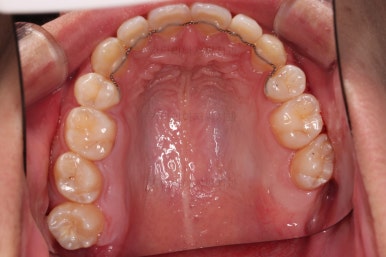

초진 시 입안의 모습입니다.

앞니가 많이 삐뚤고, 송곳니가 부각되어 덧니처럼 보이네요.

장치를 처음 부착한 모습입니다.

이번 환자분이 선택하신 장치는 데이몬 클리어라고 하는 자가결찰 세라믹 장치인데요.

흔히들 아시는 클리피씨 장치 등등에 비해 현존하는 브라켓 중에 가장 심미적인 장치입니다.